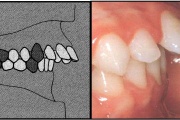

Ravijärgne seis. Jäävhammas on täielikult lõikunud.

Normaalse jäävhammaskonna pilt küljelt ja eest vaadatuna.